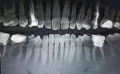

Здравствуйте! Треснул зуб 7-ка. Он был депульпирован, каналы запломбированы 6 лет назад. Откололась примерно 1/3, она в десне и шатается, вторая часть стоит крепко. Есть ли какое-то временное решение, так как сейчас нахожусь не дома и к своему стоматологу смогу попасть только через 1-2 месяца. Спасибо!

Если стенка сломалась под десну, то к сожалению такой зуб удаляется. Так что не тяните и не терпите боль, обратитесь к врачу и если мое предположение подтвердится то удалите зуб.